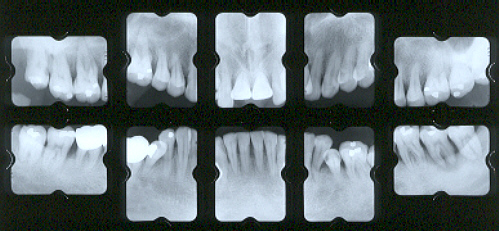

初診時 メインテナンス時

初診時

メインテナンス時